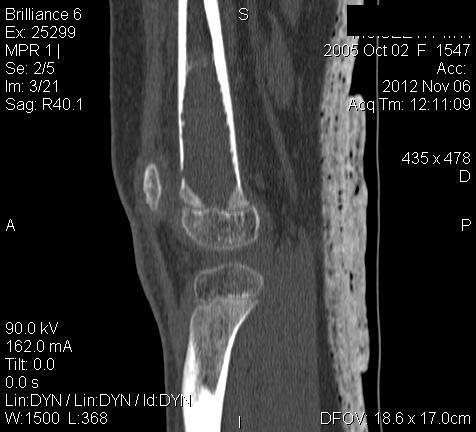

3 месяца назад в отделении была прооперирована девочка 7 лет с клинико- рентгенологической картиной аневризмальной кисты (открытая биопсия). Гистологическое заключение местных гистологов и ФНКЦ им. Д. Рогачева -аневризмальная киста. 2 недели назад девочка взята на костную пластику - на операции полный лизис костной ткани циркулярно на протяжении 10 см от эпифиза на 10 проксимальней и массивное артериовенозное крововтечение из оставшейся надкостницы . Операция закончена наложением стержневого аппарата и остановкой кровотечения тахокомбом, тампонадой мышцами. Повторная гистология неоднозначна. ФНКЦ им. Д. Рогачева дает прежний результат , ФГБУ РОНЦ НН Блохина -телеангиэктатическая остеосаркома, онкологи из института Герцена - киста .Как быть дальше. Кому верить и что делать? Заранее благодарен.

Судя по рентгенам и КТ, больше похоже на саркому, так как границы опухоли размыты. Аневризмальная киста обычно находится не по центру кости, а с одного края. Результаты гистологии надо всегда смотреть вместе с рентгенами. Если в каких-то из трёх центров видели только гистологию, то имеет смысл попросить их посмотреть и рентгены с КТ. Ежели всё видели и заключение не меняется, то можно попробовать послать в какой-нибудь очень крупный онкологический центр вроде Instituto Ortopedic Rizzoli в Италии или Mayo Clinic в США.